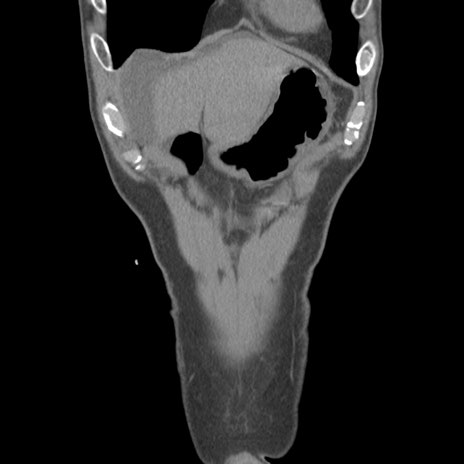

症例56 CT(冠状断像)

脂肪ウインドウ

横断像